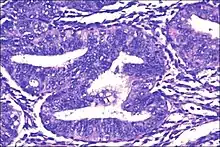

| Micrograph showing simple endometrial hyperplasia, where the gland-to-stroma ratio is preserved but the glands have an irregular shape and/or are dilated. Endometrial biopsy. H&E stain. | |

Like other hyperplastic disorders, endometrial hyperplasia initially represents a physiological response of endometrial tissue to the growth-promoting actions of estrogen. However, the gland-forming cells of a hyperplastic endometrium may also undergo changes over time which predispose them to cancerous transformation. Several histopathology subtypes of endometrial hyperplasia are recognisable to the pathologist, with different therapeutic and prognostic implications.[3]

- Endometrial hyperplasia (simple or complex) - Irregularity and cystic expansion of glands (simple) or crowding and budding of glands (complex) without worrisome changes in the appearance of individual gland cells. In one study, 1.6% of patients diagnosed with these abnormalities eventually developed endometrial cancer.[6]